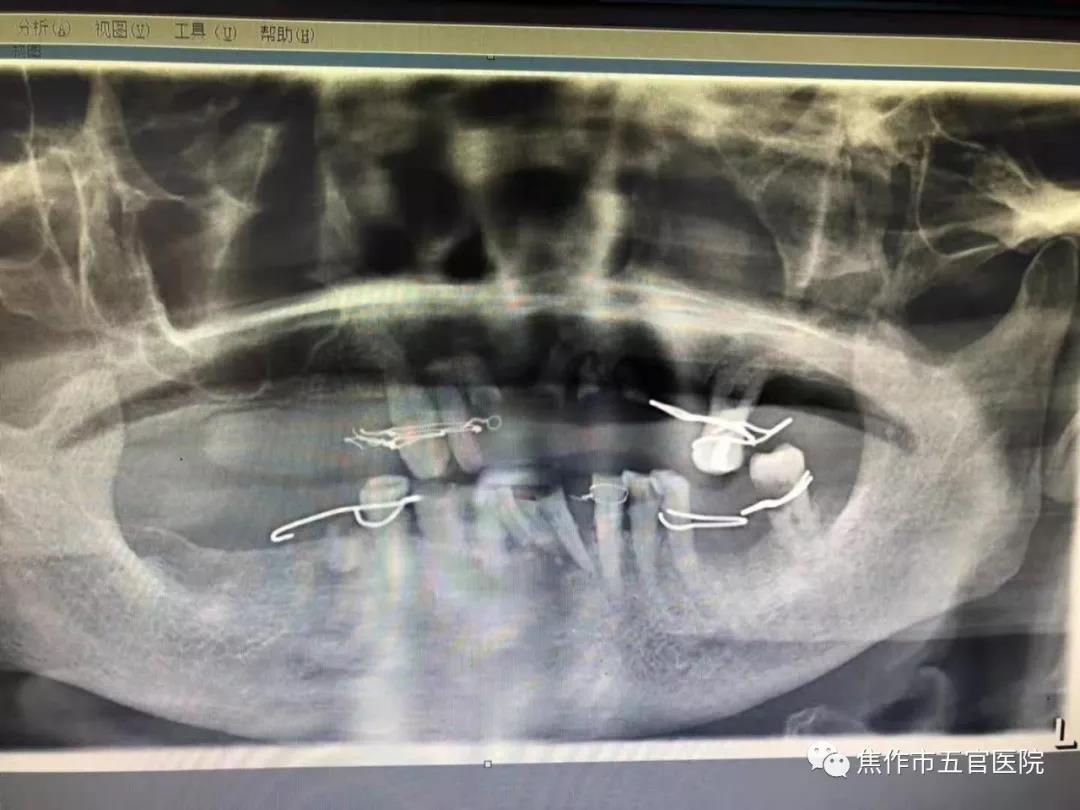

近日焦作市五官医院口腔科郭红怡医生接诊了一位84岁老奶奶,一位去过很多地方看牙,却被很多地方推脱的老奶奶。在集市花一千元捏了满口假牙,却疼了几天几夜无法吃饭睡觉,牙龈已被这些假 ...